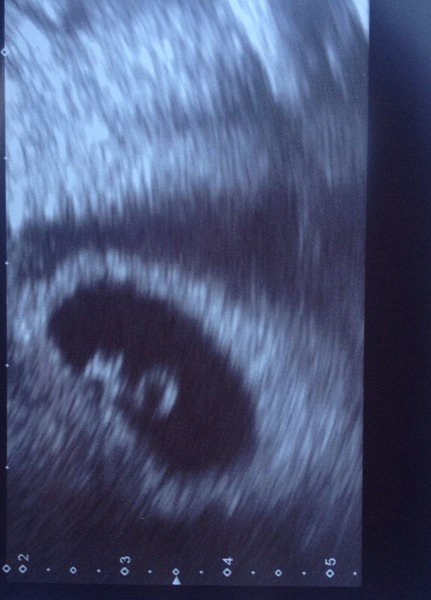

So today I have a scan due to previous dull ache which was a corpus luteum cyst... this is now Haemorrhagic/collapsing - that is a good thing even thought it sounds a bit nasty.

They have now dated me 6+2.....I thought I was nearer 7 but i only ever new my last ovulations date not previous period.

attached is baby with a heart beat :)